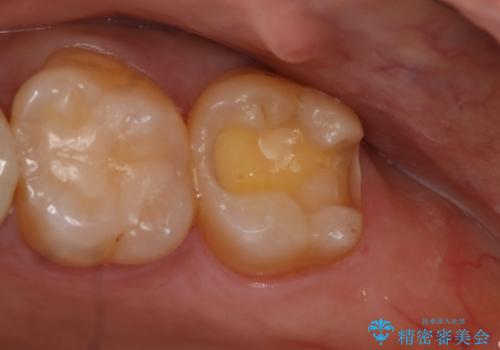

- 左上7番の銀歯のやり変えを希望された患者様です。

セラミックでの治療を希望されたため切削量などを考慮し、セラミックインレーでの治療を計画しました。

銀歯を除去し形態を整えたのち、印象しています。